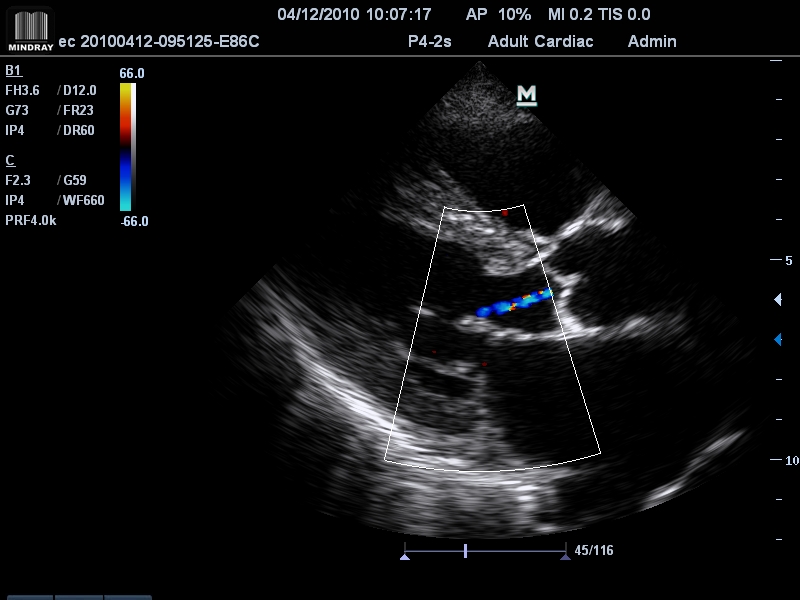

- Секторный фазированный датчик P4-2s, 1,3 - 4,7 МГц(2.0, 2.5, 3.0, H3.2, H3.6), 23.4 мм, 64 элемента